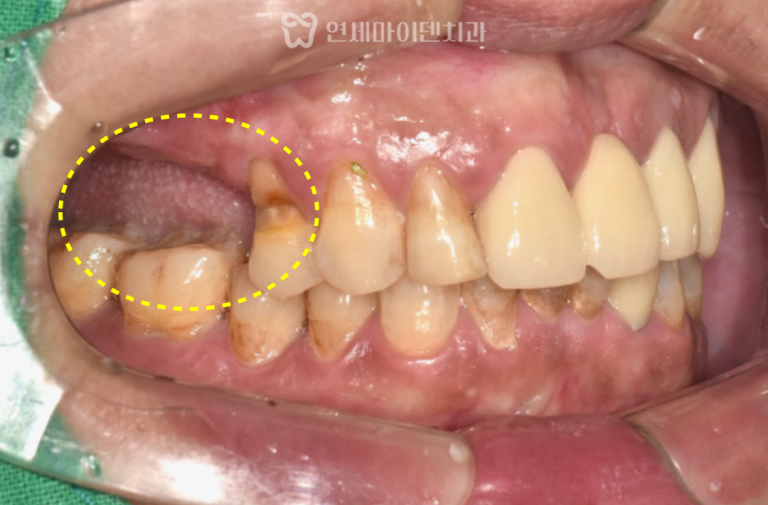

안녕하세요, 소중한 치아를 지키는연세마이덴치과 닥터꼬집 입니다. 오늘은 치경부 마모증과 잇몸 패임으로 인한 염증으로발치 진단까지 받았던 환자분의…